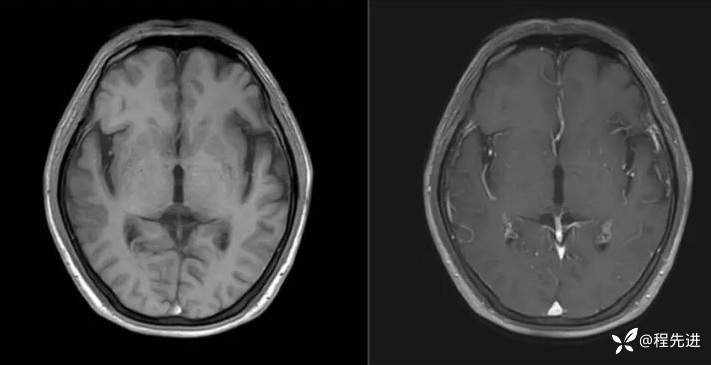

T1、T1增强: